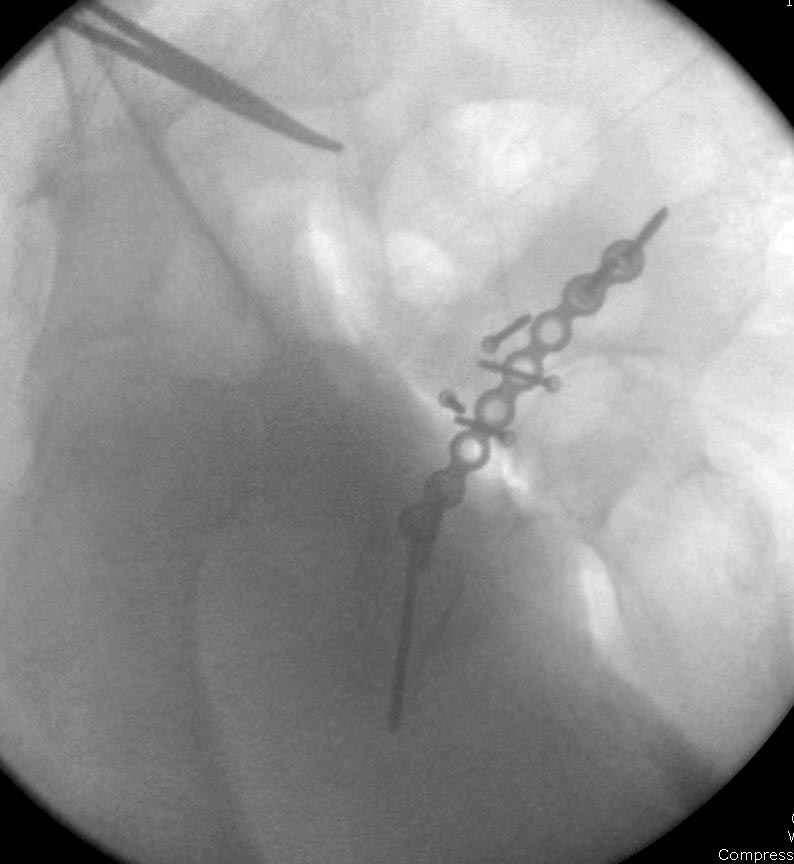

Интраоперционные N5 косая запирательная и N6 подвздошный снимок

Работаем вместе с хирургами-травматологами (в штатах все травмированные больные поступают, как больные хирургической службы, ортопед выступает в качестве консультанта), т.е. мы даем рекомендации о проведении профилактики тромбоза, совместно решаем о проведении фильтра - вена кава фильтр (см. приложение).

Если вена кава фильтр, хирурги проводят эту процедуру, а медикаментозную профилактику назначаем сами.